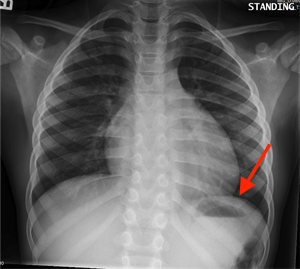

What's the part marked on the CXR?

Diaphragm, distal by it is the stomach and the dark area in the stomach is air.

Diaphragm. Below that is air filled fundus of stomach

Traube's space where the fundus of the stomach is found.